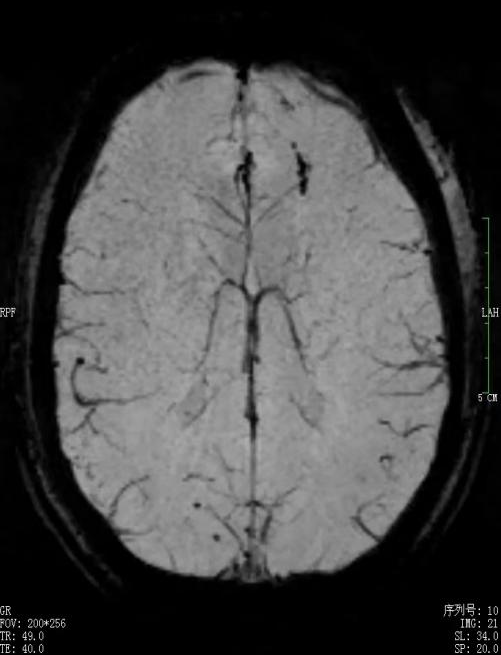

血管造影